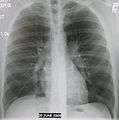

| A chest X-ray showing a very prominent wedge-shape bacterial pneumonia in the right lung. | |